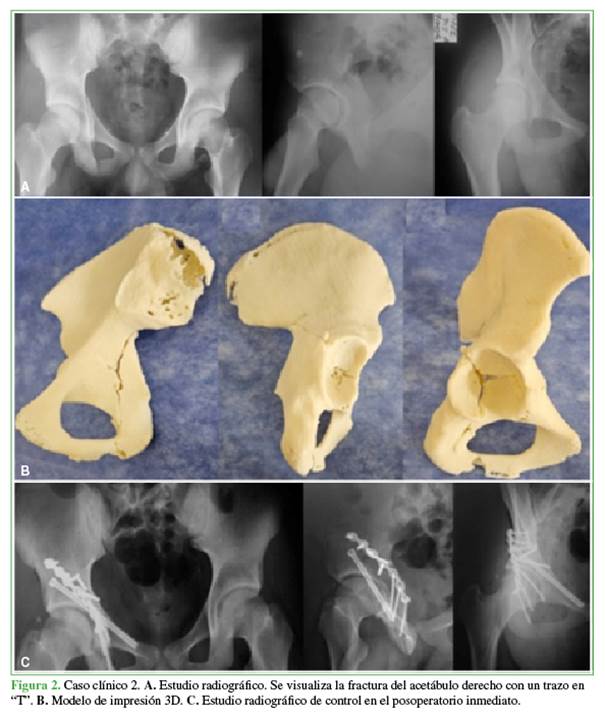

Caso clínico 2

Varón de 16 años de edad que ingresó en el Servicio de Urgencia luego de sufrir un accidente en la vía pública (motocicleta). Tenía una fractura del acetábulo derecho con un trazo en “T” transverso yuxtatectal con trazo de fractura alto en la columna anterior (clasificación AO 6.2-B.2) (Figura 2A). Se procedió a la reducción y osteosíntesis con placa de reconstrucción de 3,5 mm y un tornillo canulado de 6,5 mm, y se diseñó el modelo de impresión 3D para la planificación quirúrgica. La cirugía se realizó a los nueve días de la fractura (Figura 2B y C).

La planificación quirúrgica con el modelo 3D permitió evaluar, con precisión, la anatomía de la fractura y planificar la reducción. Durante la operación, ayudó al equipo quirúrgico a guiarse en la anatomía de la fractura y a la correcta colocación de los implantes.